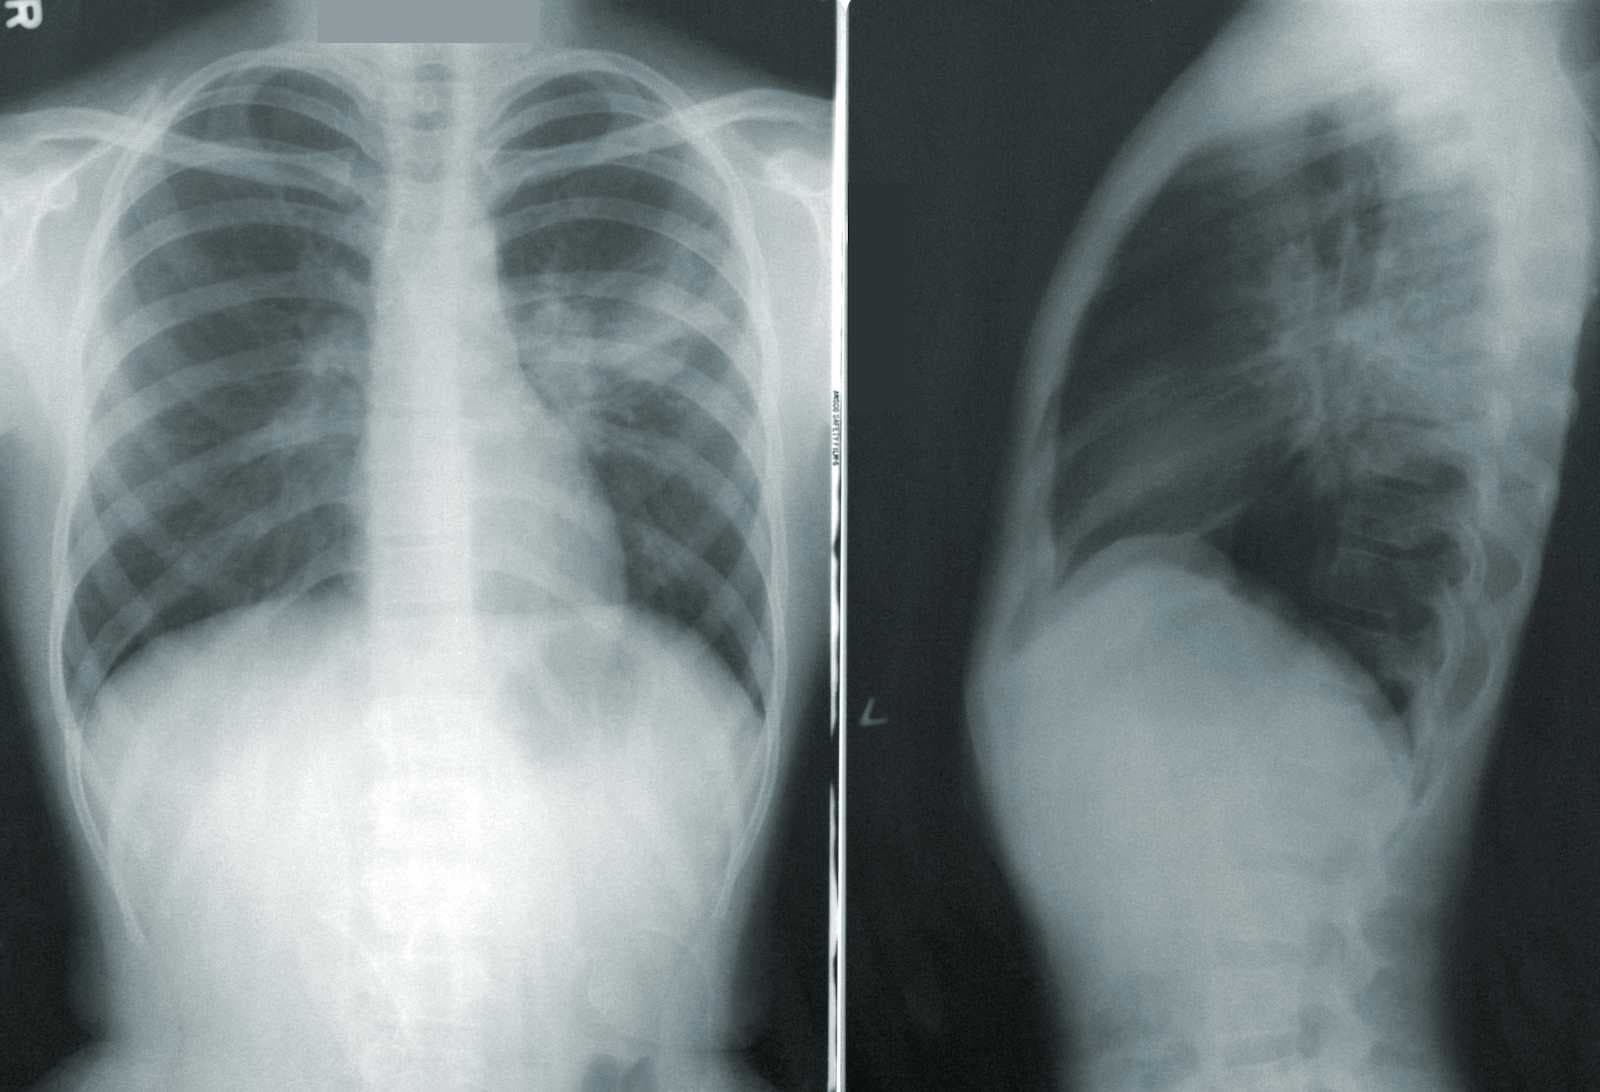

If you've tried asking ChatGPT to interpret a chest X-ray, you know the answer: it can't. Not because the technology doesn't exist, but because most general-purpose models weren't built for medical imaging. That's changing fast. A new generation of v...